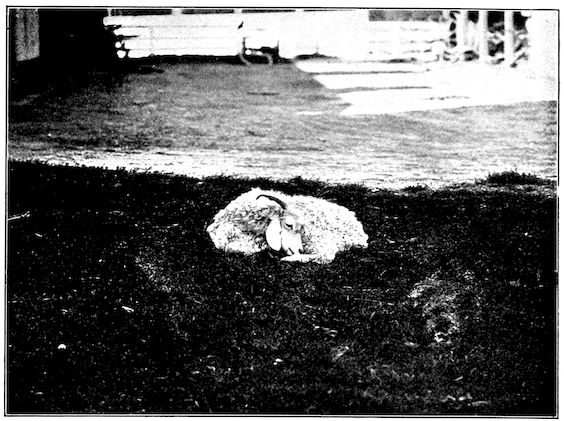

Fig. 2.—Horse suffering from osseous cachexia.

2. The second phase is characterised by more precise signs, which become almost pathognomonic. Difficulty in rising is added to the already existing tendency to remain lying, and to the interference with movement.

When lying down the patient no longer responds to the trifling stimulus, which a healthy animal needs to cause it to rise. It remains languid and apparently lazy, though in reality it experiences pain and difficulty on attempting to get up. The least muscular effort when lying down often causes it to moan, as do efforts to change its position or to walk. Even when standing still, it may appear to be in pain, and patients often assume a position similar to that of a horse suffering from laminitis.

At the end of this second phase, swellings appear, due to synovitis or arthritis of the extremities, synovitis of the sesamoid or navicular sheaths or to inter-phalangeal arthritis or arthritis of the fetlock joint. Weakness becomes marked, and the appetite is very irregular.